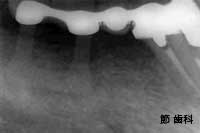

② これは右上の奥歯を2本連続して失った部位に対して、最後臼歯部分にT字型をした“人工サファイヤ”タイプのインプラントを施し、その手前の2本の歯とブリッジ状に連結する事で欠損補綴を行っています。やはり、上記と同時期のものです。

③ これも上の症例と同じものですが、インプラントの底部が上顎洞底線にタッチするように埋入処置が行われていることが確認できます。当時の“人工サファイヤ”タイプのインプラントは、「単独植立」を前提としておらず、隣在歯と連結するやり方が基本となっていました。